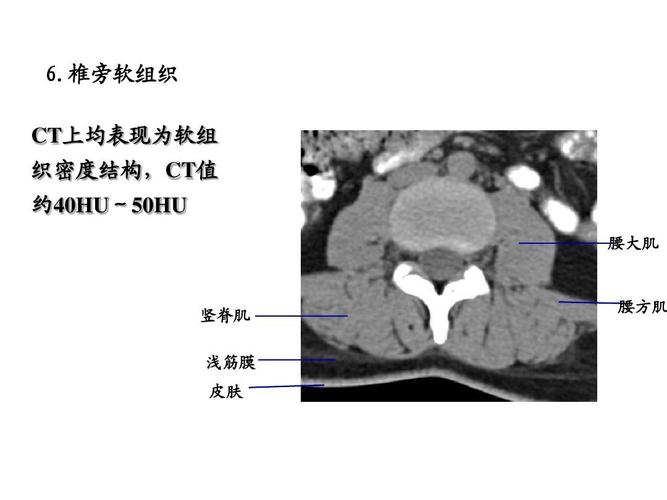

ct上均表现为软组 织密度结构,ct值 约40hu~50hu 腰大肌 竖脊肌 腰方